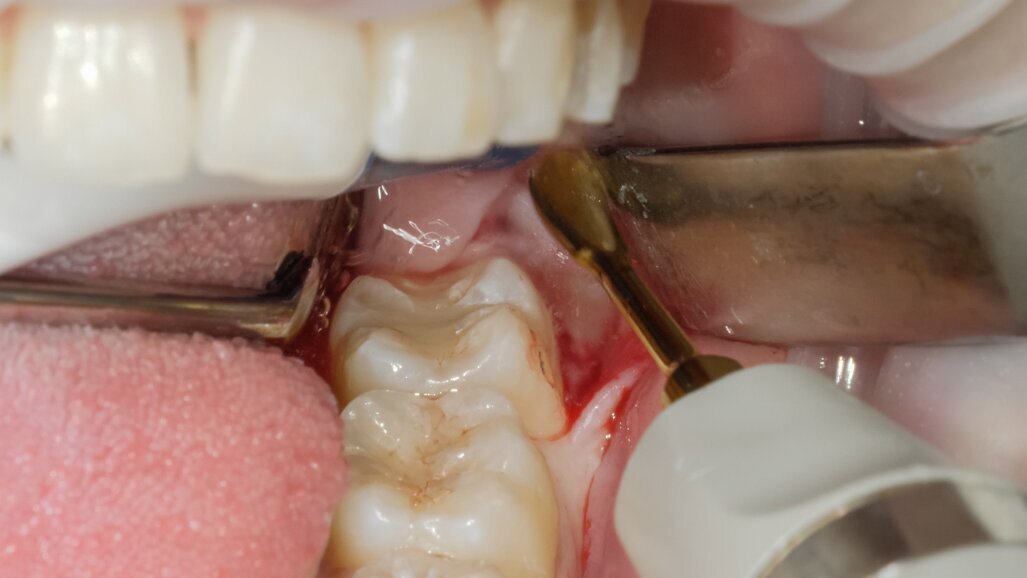

L’ostectomia di accesso per evidenziare la corona è stata praticata mediante inserto SLO-H. Questo inserto nasce per il disegno della botola ossea nel rialzo di seno laterale, ma per la sua forma e il forte potere tagliente risulta molto efficace anche nella ostectomia peridentale (Figg. 3, 4). Mediante fresa a fessura in carburo di tungsteno montata su manipolo diritto sotto costante irrigazione di fisiologica sterile si è proceduto alla fase di odontotomia verticale in modo da separare la porzione corono radicolare mesiale da quella distale (Fig. 5).

La scelta condivisa è quella di utilizzare la tecnologia piezolettrica per le fasi di odontotomia, solo nelle zone di difficile accesso o in prossimità di strutture anatomiche a rischio come il nervo alveolare inferiore. Per la fase di lussazione si è applicato il protocollo descritto da Fontanella utilizzando il nuovo inserto EXL1 (Figg. 6, 7). Questo inserto insieme agli altri due inserti lussativi (EXL2, EXL3) hanno la particolarità di sfruttare l’impulso piezoelettrico associato al movimento lussativo dell’inserto montato sul manipolo. La cavità residua è stata gestita rimuovendo i residui di sacco follicolare e detergendo il sito post estrattivo sfruttando l’effetto cavitazionale della tecnologia piezoelettirca (Fig. 8). Il lembo riposizionato è stato suturato con chiusura per prima intenzione con punti singoli riassorbibili 4/0 (Fig. 9). Al controllo post operatorio la ferita presentava una guarigione nella norma, e la paziente riferiva un post operatorio senza particolare gonfiore e con assunzione di antidolorifico solo nel primo giorno post chirurgico